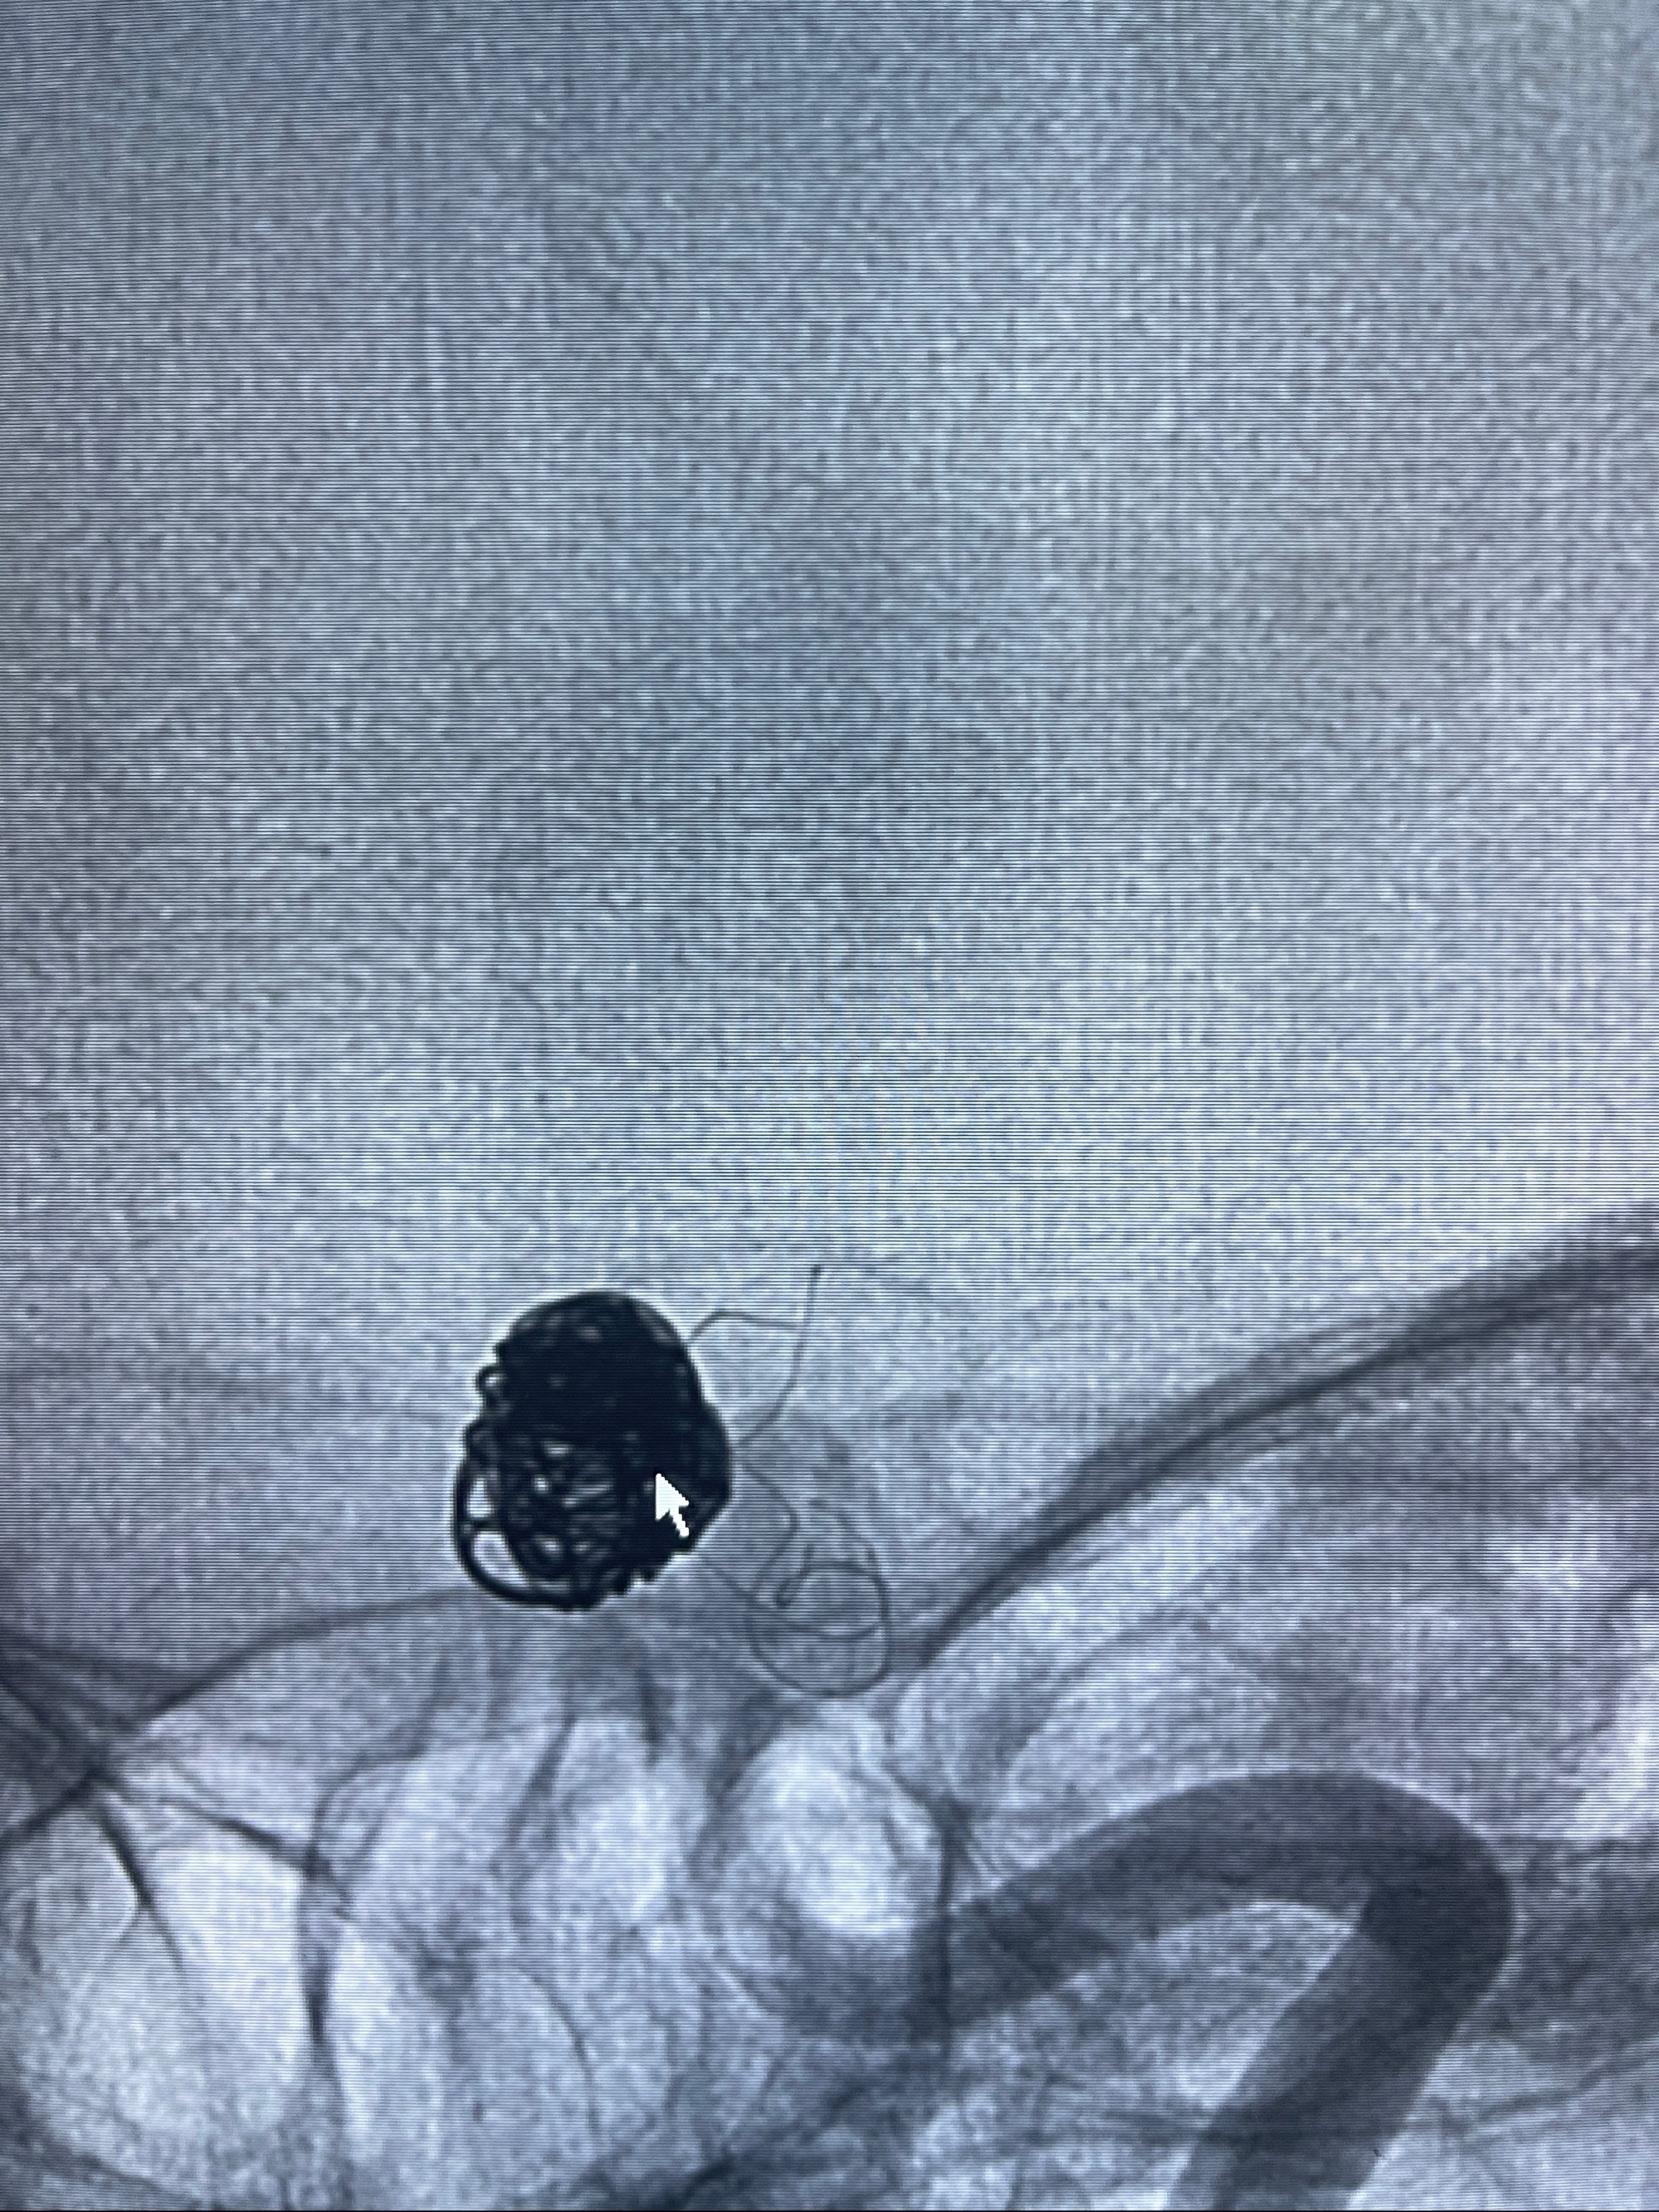

- Tubridge 4.0-20mm密网支架

- 加奇微弹簧圈:7*30/6*20/5*20/2*8

术后3D显示支架贴壁佳